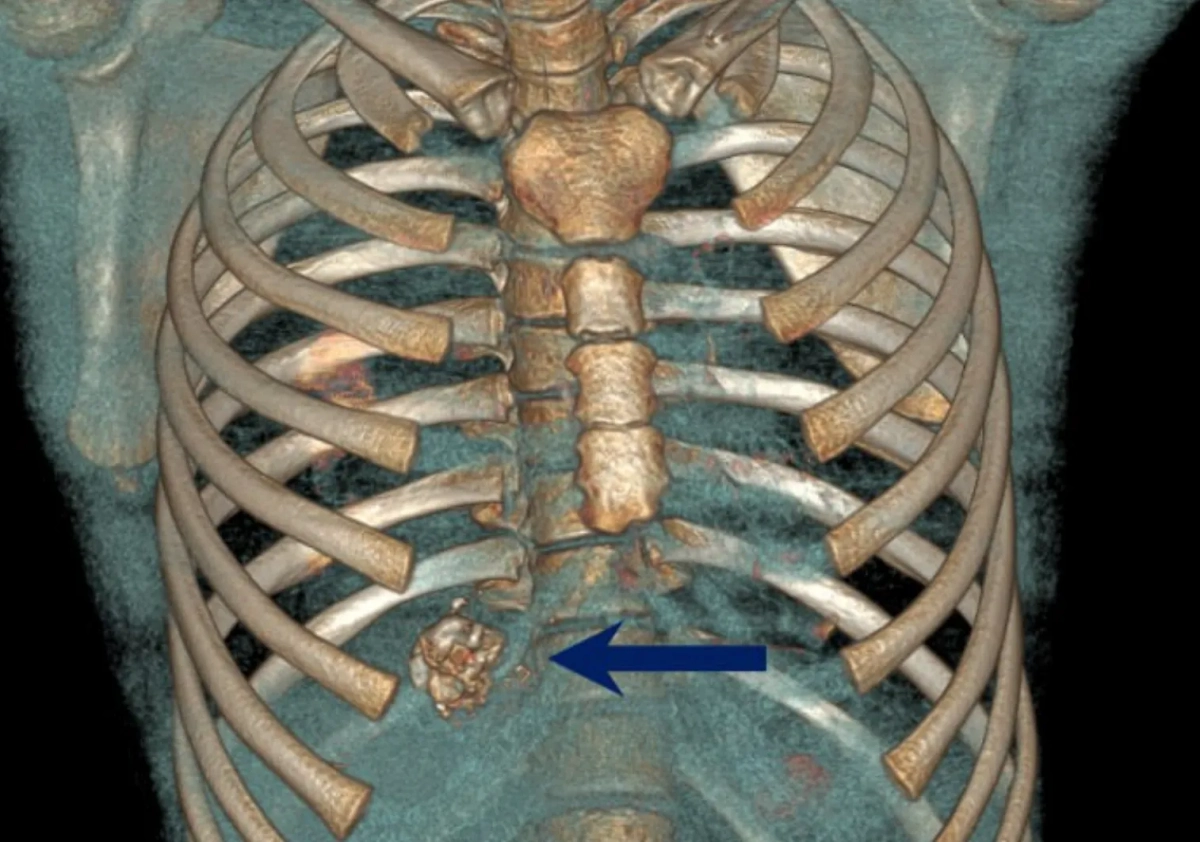

ЧП произошло в новогоднюю ночь. За пару часов до полуночи мальчик отправился с друзьями запускать салюты. Они засунули петарду в трубу, подожгли заряд и отбежали, однако во время взрыва школьник почувствовал сильную боль в груди и упал. Пострадавшего тут же госпитализировали. Врачи оценили состояние пациента как крайне тяжёлое. Инородные предметы пробили одежду и вошли в тело, но, к счастью, крупный элемент сработал как заглушка, не давая ребёнку погибнуть от потери крови. Также взрывом было повреждено ребро.

«Парню повезло, что не было повреждения висцеральной плевры, что лёгкие и диафрагма целы, не было напряжённого гемо- и пневмотракса. Фрагменты инородных тел удалили при ревизии плевральной полости. Раны ушили и поставили плевральный дренаж», — рассказал врач-хирург отделения хирургии № 4 Сергей Мороз.